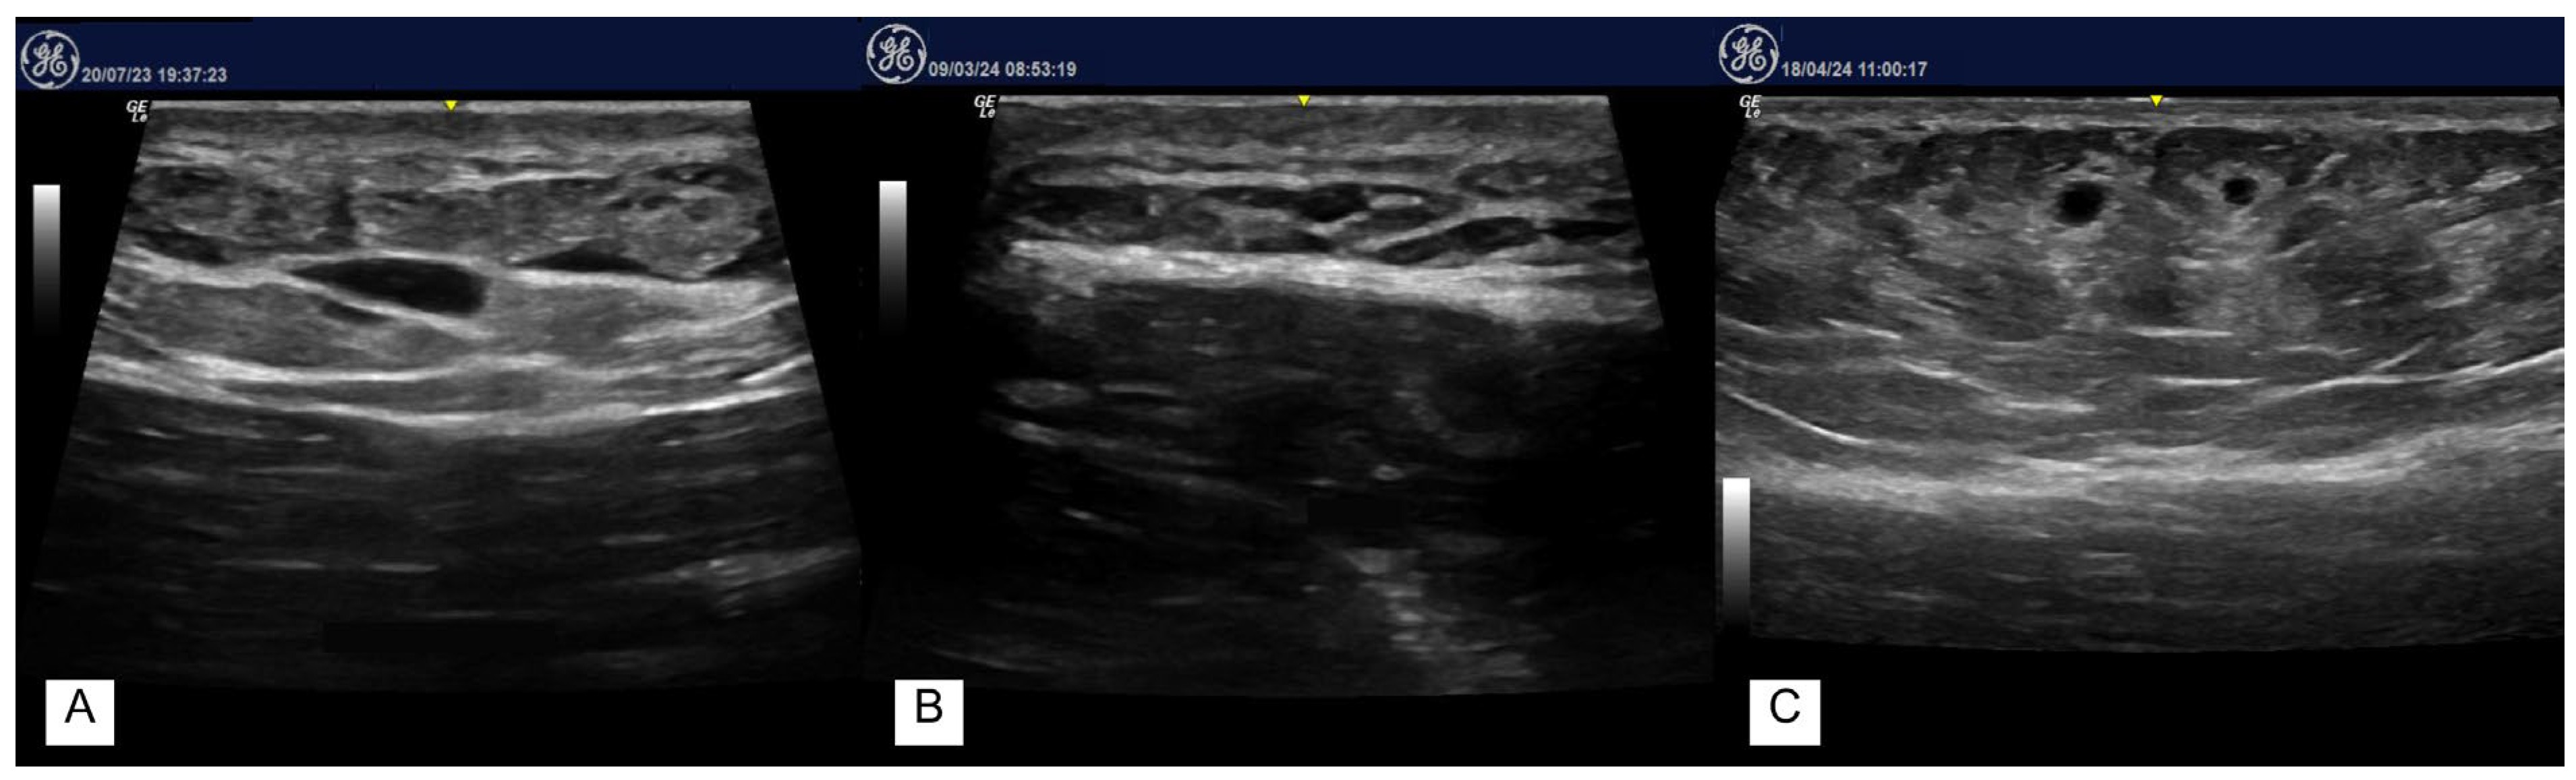

女性4年前接受過膠原蛋白注射。因額部可觸及腫塊,超音波檢查(A)額部橫向掃描看見圓形低迴音結節。

值得注意是,HA在超音波影像是低回音/近無回音,但更接近水袋/果凍袋的囊樣表現,後方回音增強。

而膠原蛋白注射後多年出現的腫塊,屬於異物反應/肉芽腫/纖維化形成的實質性結節,也會呈現低回音,但影像偏向實心結節、邊界可能不規則,內部混雜回音,後方不一定有典型增強。

因此,醫師掌握超音波的經驗判斷就很重要。

雖然隨時間推移,可觀察到玻尿酸凝膠量的減少,其特徵為凝膠口袋數量與體積的下降,但仍持續可見多個呈現假性囊腫樣(pseudocystic appearance)的低回音結構,直到20個月都還可以看到玻尿酸在組織裡面。上圖為多頻率超音波影像,顯示在 12 個月(A)與 20個月(B、C) 追蹤時,臀部內可見之玻尿酸口袋。

一名47歲的女性接受唇部注射後一周,超音波檢查結果顯示低迴聲區域,(A) 圖為降解酶治療之前的超音波;(B)圖為降解酶治療之後的超音波,三週後複查影像顯示纖維化消退,低迴聲區域周圍僅殘留輕微水腫。

一名53歲的女性接受法令紋注射, (A) 圖為10天後超音波檢查結果,顯示存在深部低迴聲結節;(B) 圖為口服抗生素,同時降解酶治療9週後再檢查,超音波顯示完全恢復。